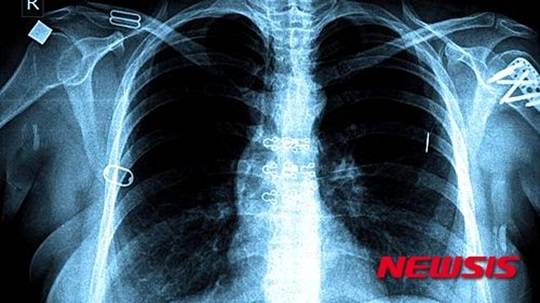

결핵 잠복감염, 보육시설-학교서 3년간 1만347명 감염

[티브이데일리 신상민 기자] 최근 3년간 보육시설과 교육기관에서 발생한 결핵으로 1만명 이상이 결핵 잠복감염 된 것으로 집계됐다.

23일 질병관리본부에서 발간하는 ‘주간 건강과 질병’ 최근호에 따르면 2013~2015년 어린이집 등 보육시설과 초, 중, 고등학교에서 1249명의 결핵 환자가 발생했고 접촉자 18만3427명 중 5.6%가 결핵 잠복감염자로 확인 됐다.

결핵 잠복감염자 숫자는 연령이 높을수록 많다. 감염율은 연령이 낮을수록 높아지는 경향을 보였다.

감염자는 고등학교가 7425명으로 가장 많았다. 이어 중학교 1620명, 어린이집, 유치원 637명, 초등학교 609명 순으로 나타났다. 결핵 잠복감염율은 어린이집, 유치원이 14.4%로 가장 높았다. 이어 초등학교 9.2%, 중학교 5.8%, 고등학교 5.2% 순이었다.

어린이집, 유치원에서 발생한 결핵환자 중 99.2%가 교직원이었다. 초등학교도 70.5%가 교직원을 통한 감염 사례였다.

질병관리본부 관계자는 "소아는 정상 면역능을 가진 성인에 비해 결핵으로 진행할 위험이 높기 때문에 성인에 비해 적극적인 역학조사가 필요하다"고 말했다.